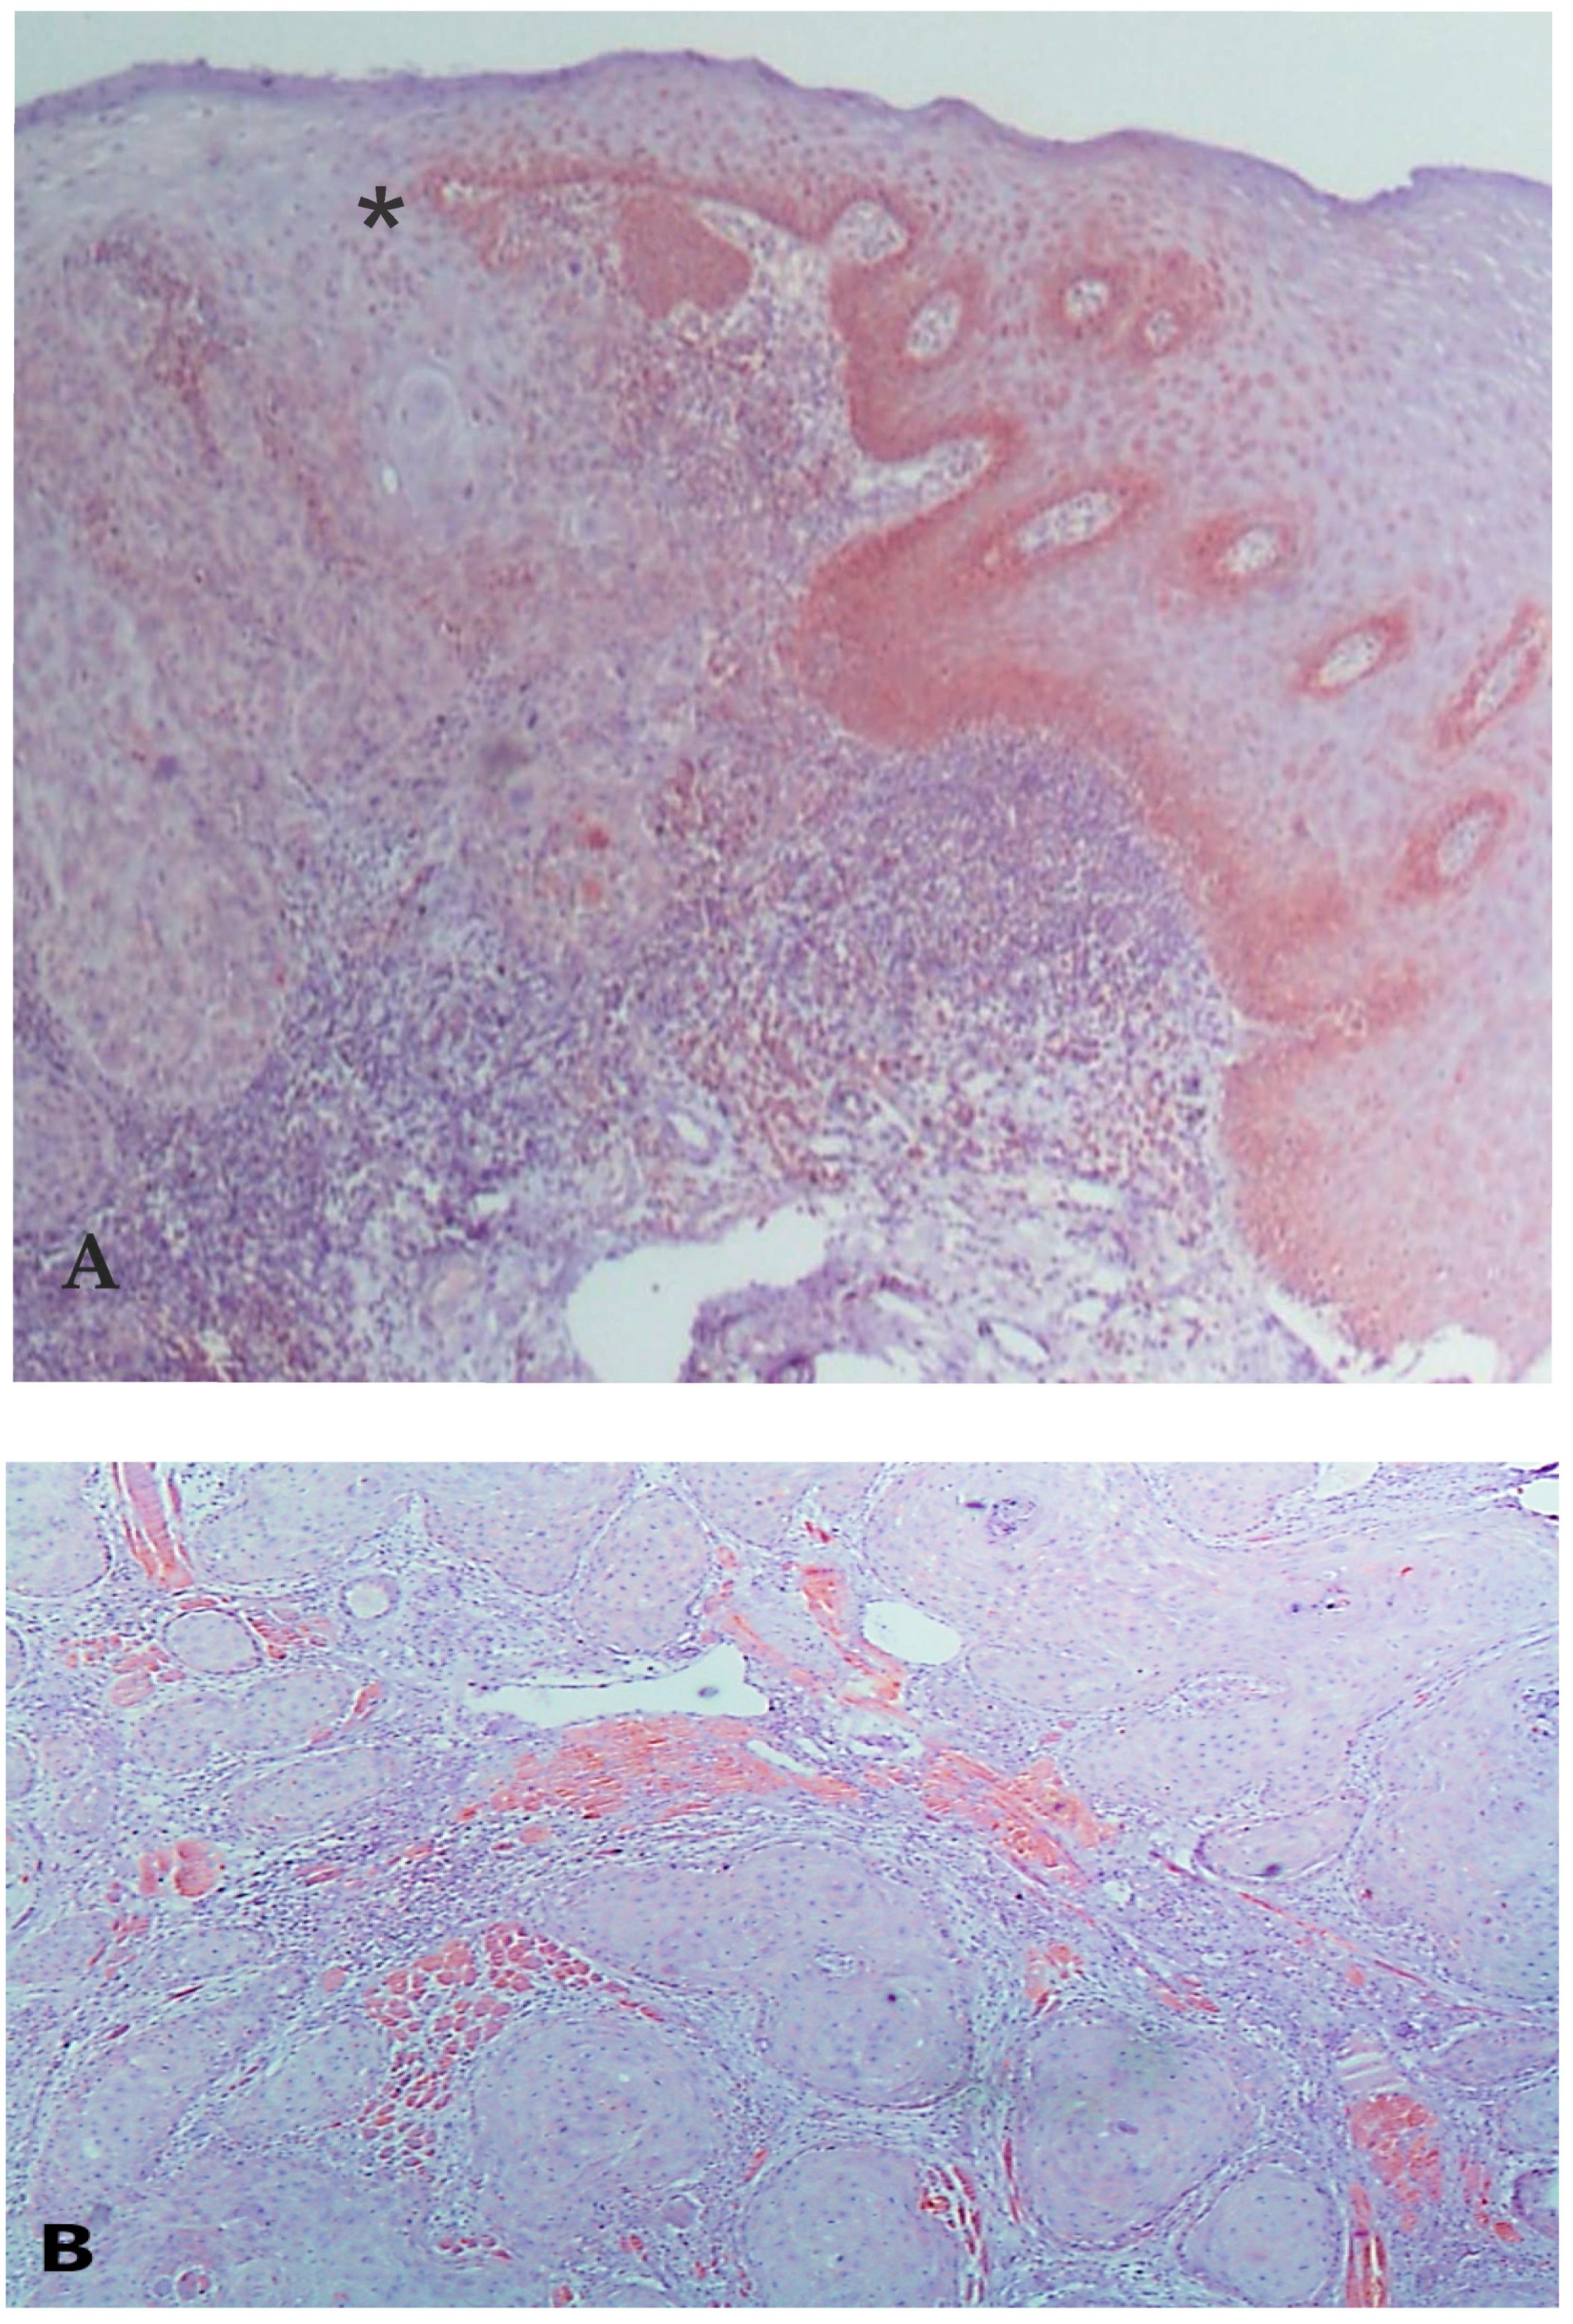

3. Results

3.3. VDAC1 Expression